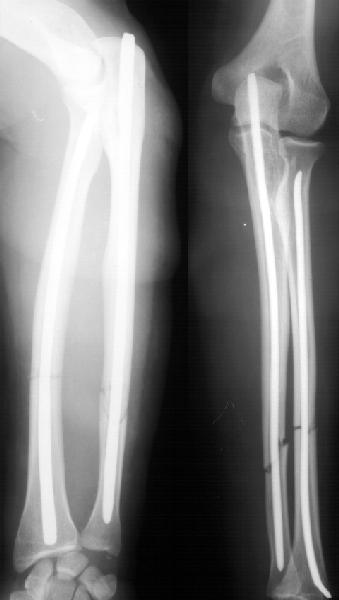

Уважаемые коллеги!Доводим до Вашего сведения наш скромный опыт применения блокирующего остеосинтеза локтевой кости (4случая), четверо пациентов с ложными суставами локтевой кости. Во всех случаях оперировали открыто с костной аутопластикой.Технических проблем введения штифтов не было. В одном случае отвалилась резьбовая часть спицы при прокс. блоке (оставлена как блокирующий винт). Дистальное блокирование осуществляли используя вместо кондуктора сп. Киршнера изгибая ее конец о край кондуктора на необходимую длину до отверстий. Наши первые впечатления классные. Очень быстрая функциональная реабилитация без гипса и консолидация через 2 мц. На представленных фотографиях двое пациентов.Тот, у которого якобы не срастается лучевая кость на АО пластине, уже катался на горн. лыжах, а сейчас опять уехал на Эльбрус -экстремал ,,,нов. С уважением Нагога Александр, ортопедическая клиника ОРТО, Самара.